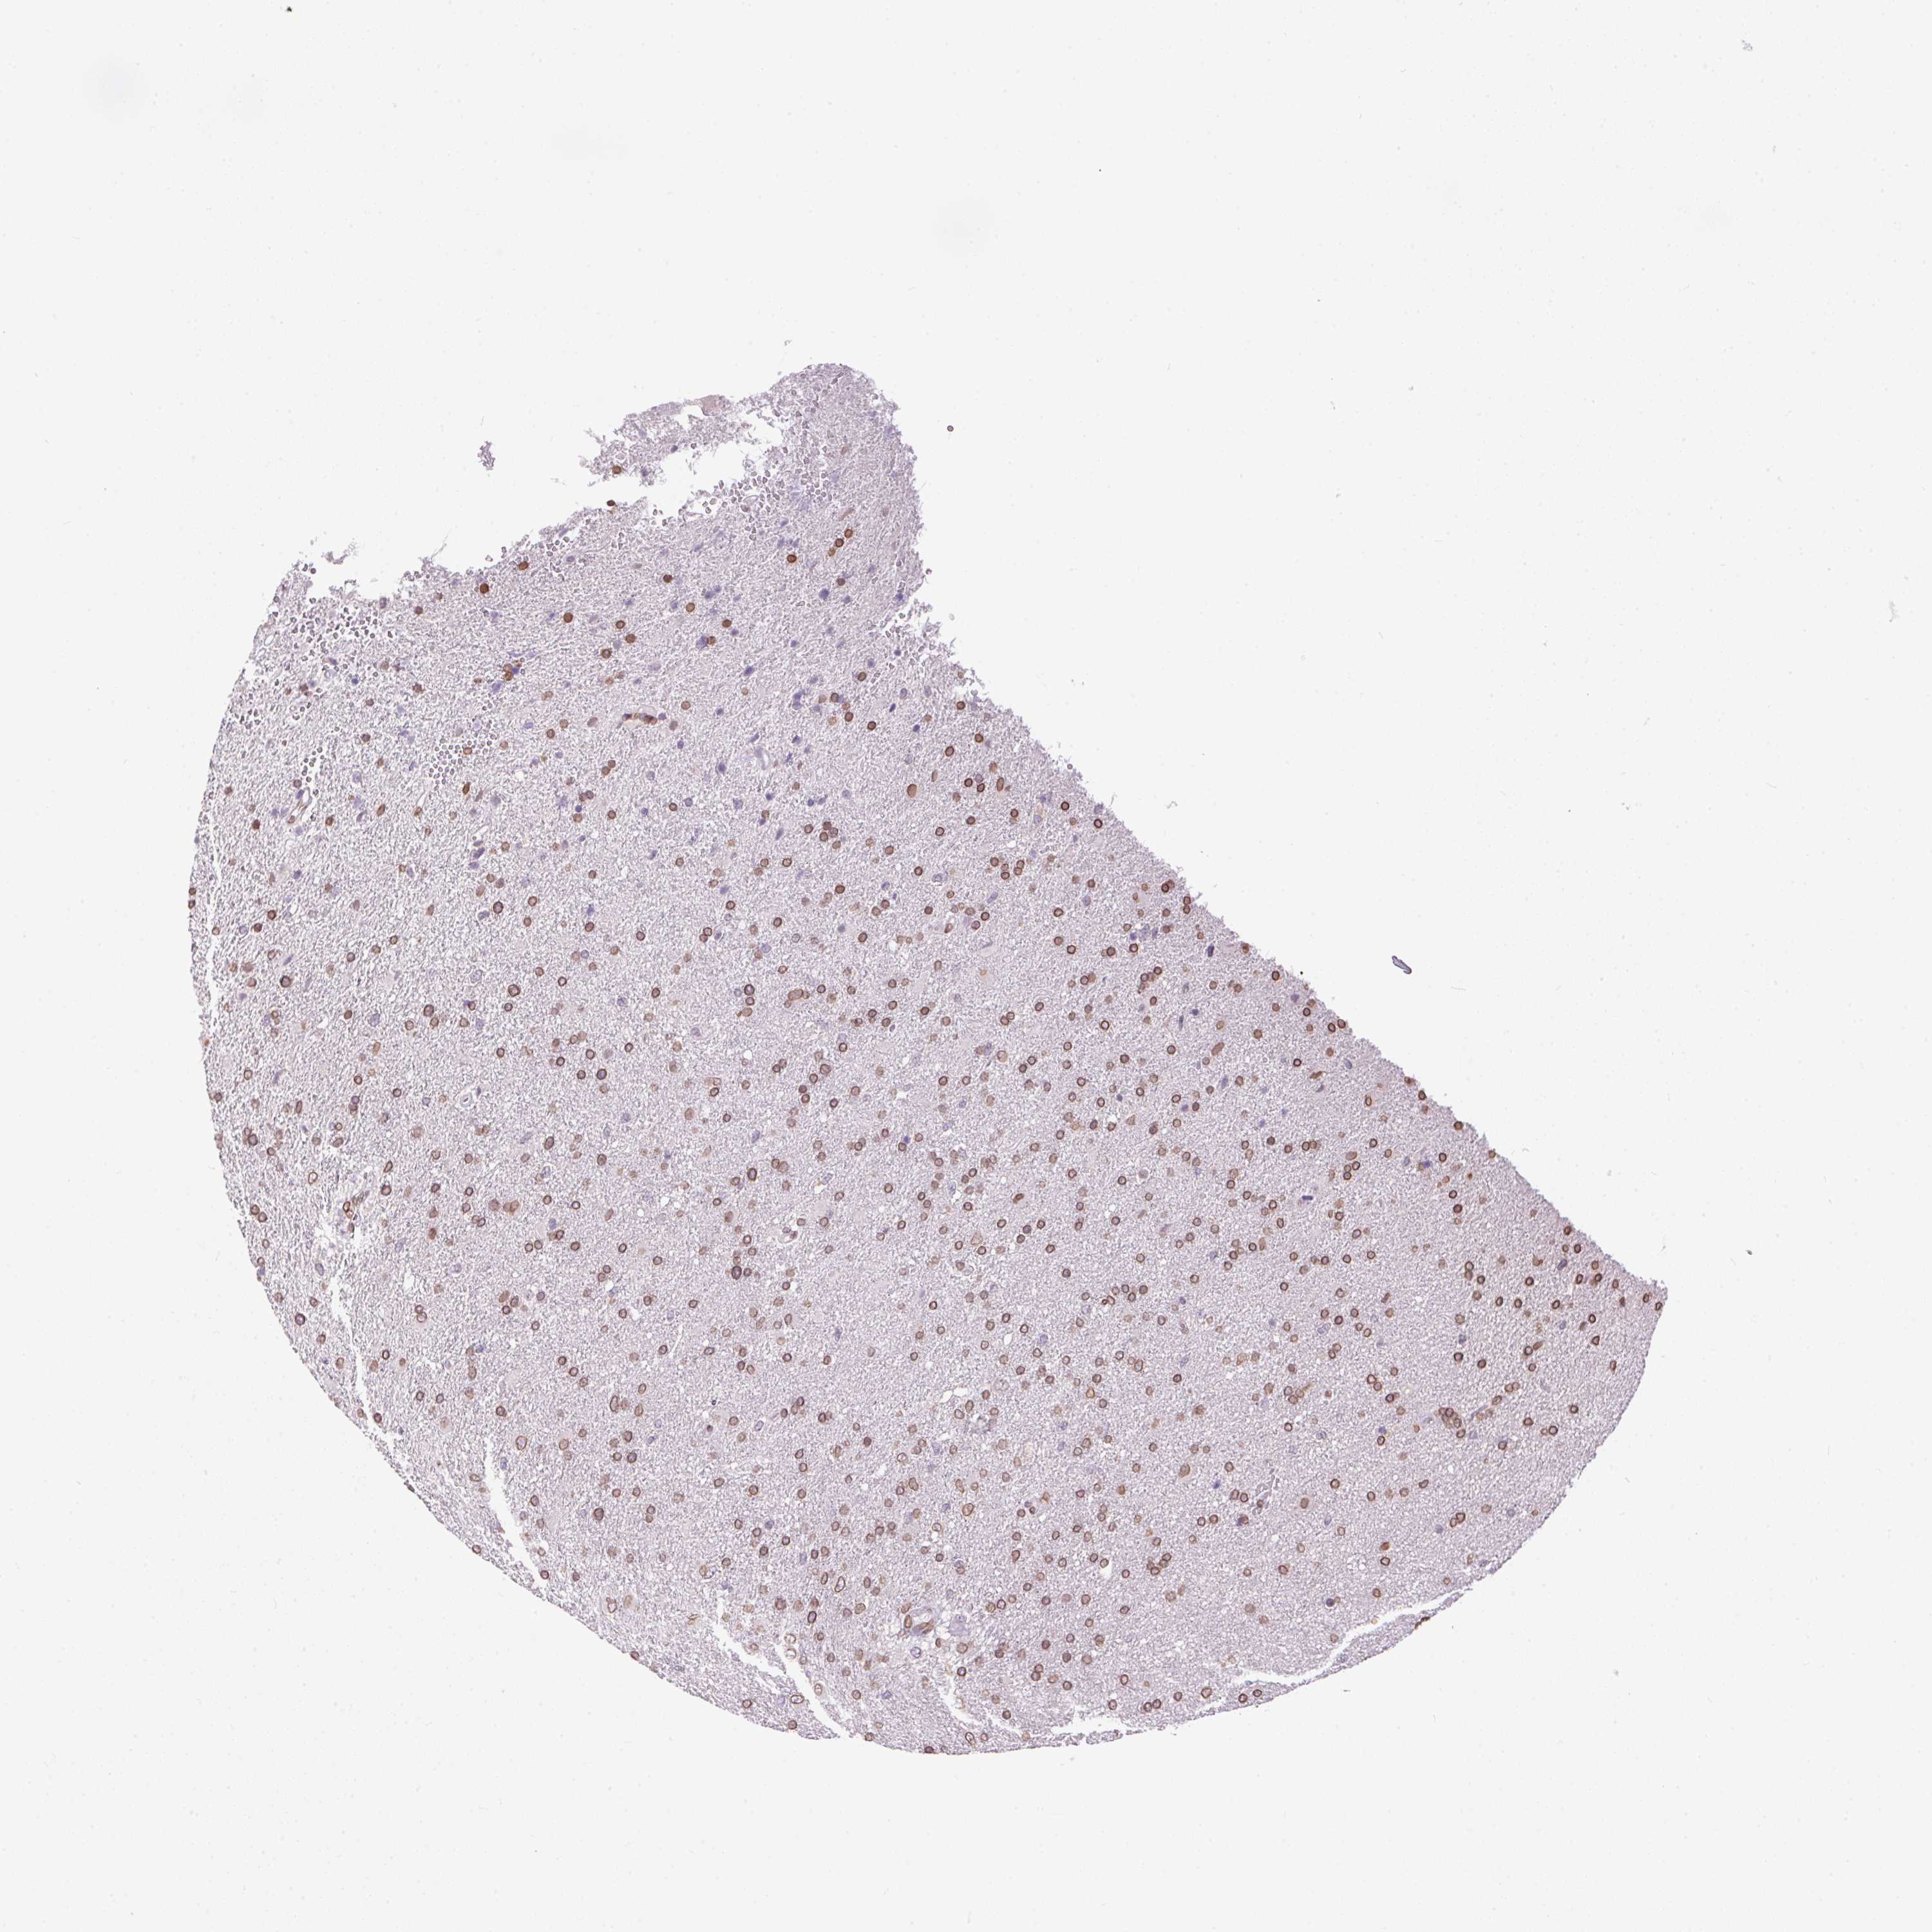

GLIOMA - Protein expressioni

A mouse-over function shows sample information and annotation data. Click on an image to view it in a full screen mode. Samples can be filtered based on level of antibody staining by selecting one or several of the following categories: high, medium, low and not detected. The assay and annotation is described here.

Note that samples used for immunohistochemistry by the Human Protein Atlas do not correspond to samples in the TCGA dataset.

Antibody stainingi

Antibody staining in the annotated cell types in the current human tissue is reported as not detected, low, medium, or high, based on conventional immunohistochemistry profiling in selected tissues. This score is based on the combination of the staining intensity and fraction of stained cells.

Each image is clickable and will lead to virtual microscopy that enables deeper exploration of all samples and also displays staining intensity scores, fraction scores and subcellular localization as well as patient and tissue information for each sample.

Antibody HPA057160

Staining

High

Medium

Low

Not detected

Intensity

Strong

Moderate

Weak

Negative

Quantity

>75%

75%-25%

<25%

None

Location

Nuclear

Cytoplasmic/membranous

Cytoplasmic/membranous,nuclear

Glioma, malignant, Low grade

Glioma, malignant, High grade